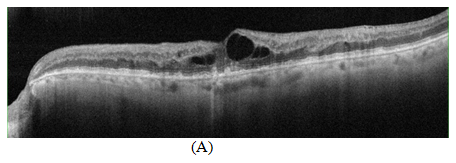

Optical Coherence Tomography (OCT) shows hyperreflectivity of inner retinal tissues along with empty cystic formation, increased central macular thickness and disturbed ellipsoid zone; RPE shows formation of hard drusen.

OCT showed remarkable thickness reduction within 48hrs with minimal cystic formation and improved hyperreflectivity in inner retinal layers, however OCT after 4weeks shows improvement in retinal structural changes with normal thickness, while results maintained in the 8weeks (Figure 2).

Figure 2 OCT scan showing (A) Cystoid macular edema with increased hyper reflectivity in the inner retinal tissue due to retinal vein occlusion with RPE alternation related to drusen formation (B) 48hrs later after suprachoroidal injection of triamcinolone acetonide showing decreased in central retinal thickness and resolution of cystic spaces (C, D) 4weeks and 8weeks OCT scans showing sustained effect of treatment with suprachoroidal triamcinolone acetonide.